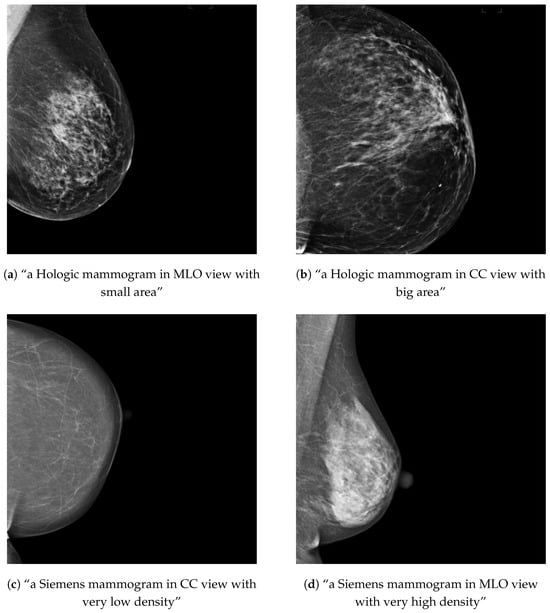

Figure 3.

Examples of training mammograms (real) and their respective text prompts for OMI-H (a,b) and VinDr (c,d).

For each healthy mammogram, a text prompt description was created and saved along with the image ID in a JSON file. In the case of the OMI-H dataset, we created a prompt with the image view and breast area size information. To compute the breast area size, we first obtained a breast mask using the intensity information of the image and then applied a threshold to separate background and breast tissue. Later, the ratio of pixels in the mask compared with the total image was computed and criteria for three different breast area sizes was defined, as shown in Table 2. For the VinDr dataset, the breast density information was included instead of the breast area for the prompt description. Breast density was available in BI-RADS scale, so we needed to transform this information into a semantically meaningful text following the criteria in Table 2, based on the BI-RADS breast density descriptions [27]. Examples of the text–image training samples can be found in Figure 3.